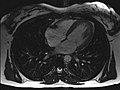

MRT des menschlichen Herzens, Vierkammerblick -

Neue, schnellere Aufnahmeverfahren ermöglichen das Scannen einzelner Schnittbilder in Bruchteilen einer Sekunde und liefern auf diese Weise eine wirkliche Echtzeit-MRT, die die bisherigen Versuche in Anlehnung an die konventionelle Fluoroskopie ersetzen. Somit können beispielsweise Bewegungen von Organen dargestellt oder die Position medizinischer Instrumente während eines Eingriffs überwacht werden (interventionelle Radiologie). Zur Abbildung des schlagenden Herzens (Abbildung rechts) werden bisher mit einem EKG synchronisierte Messungen benutzt, wobei Daten aus mehreren Herzzyklen zu vollständigen Bildern kombiniert werden. Neuere Ansätze für die Echtzeit-MRT versprechen dagegen eine direkte Herzbildgebung ohne EKG-Synchronisation sowie bei freier Atmung mit einer zeitlichen Auflösung von bis zu 20 Millisekunden.

- Schnell bewegte Organe wie das Herz lassen sich mit den meisten üblichen Geräten nur mit eingeschränkter Qualität darstellen oder erfordern eine Bewegungskompensation durch zeitliche Mehrfachabtastung. Mit Multikanalsystemen und HF-Empfangsspulen mit zahlreichen parallelbetriebenen Spulenelementen sind diese Untersuchungen durch Verfahren wie die parallele Bildgebung jedoch möglich und halten mehr und mehr Einzug in die klinische Routinediagnostik.